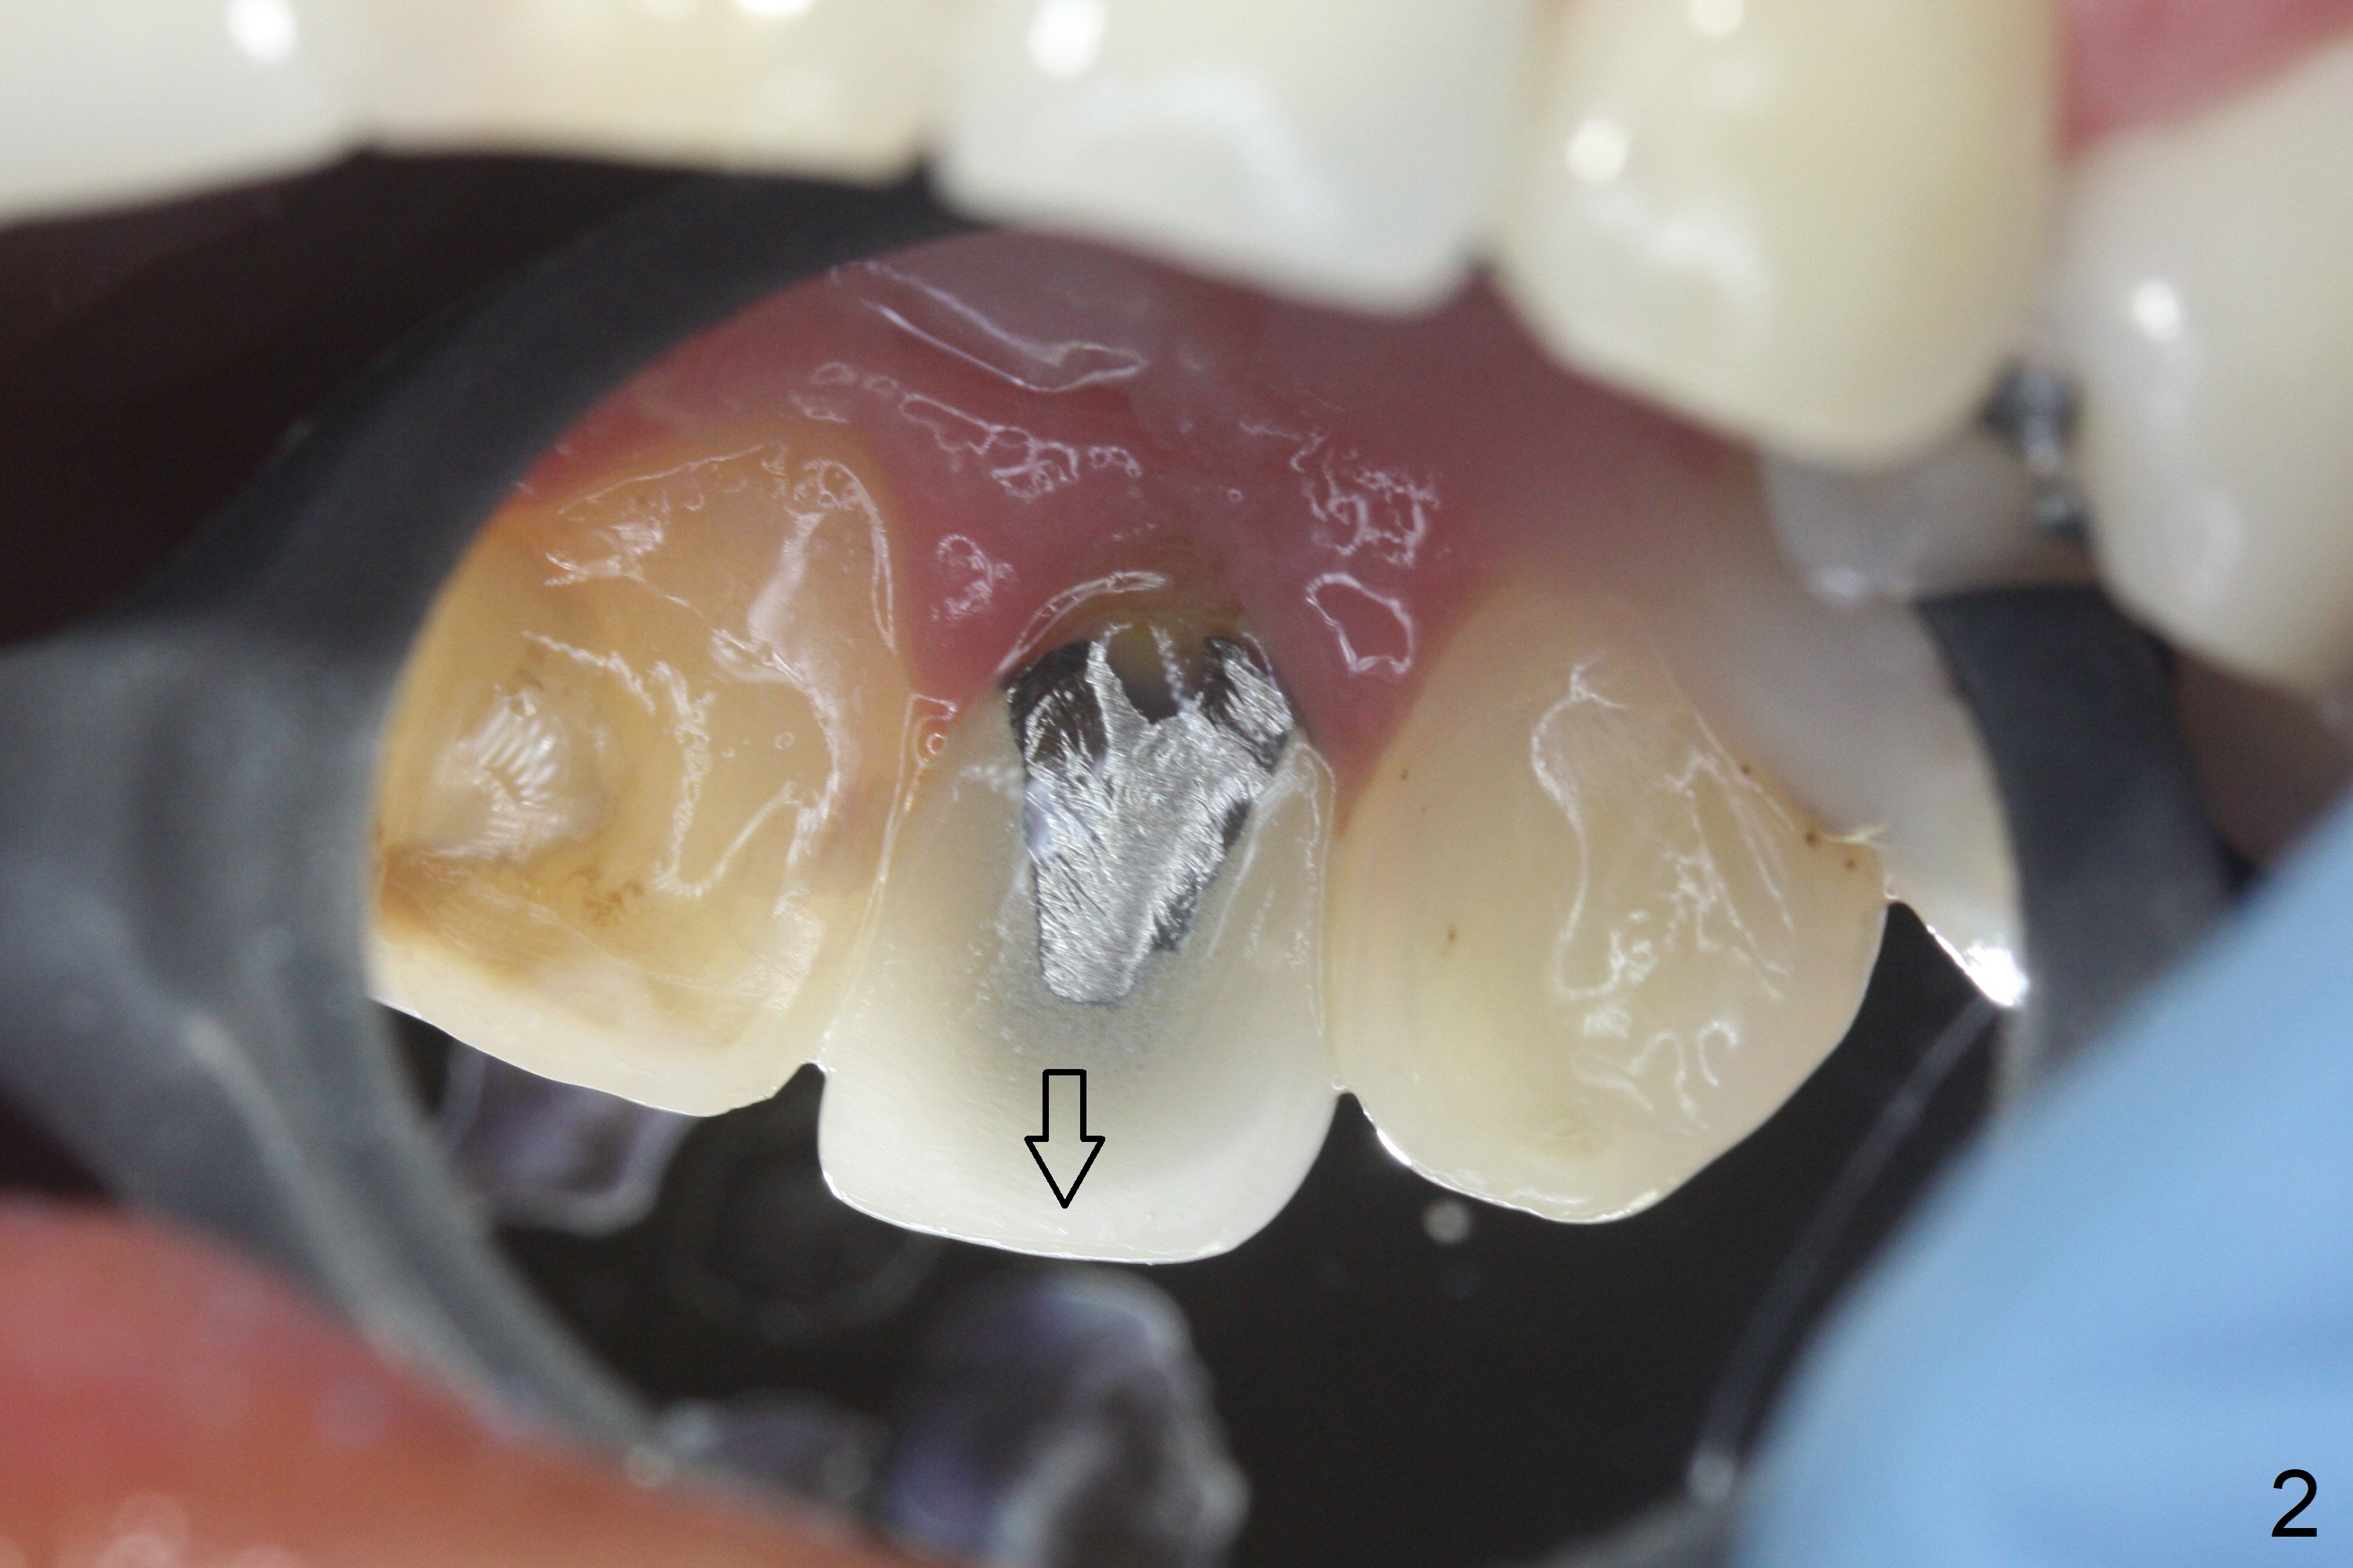

When the patient returns, the crown at #10 has displaced incisally (Fig.1,2 arrow). The initial depth is 15 mm (Fig.3, palatal gingival margin). After a 3.8x12 mm SM implant is placed (Fig.4), allograft is packed in the peri-implant space (*, as compared to Fig.3) and a 3.9x4(3) mm abutment is placed (A). More allograft is placed in the peri-abutment space (Fig.6 *). The existing crown (Fig.4,5 C) is hollowed, relined (R) and used as an immediate provisional (Fig.7-9). The patient is pleased with the appearance of the apically-repositioned provisional (Fig.7 arrow). She returns for impression 3.5 months postop (Fig.10). After change of abutment to 3.9x4(4.5) mm and new provisional, impression is retaken 5 months postop (Fig.11,12). It appears that the implant is palatally placed and a little large for the site (Fig.11 (B: buccal); Fig.12 (^: thin layer of the palatal plate)). If an angled abutment were used, a screw-retained crown might have been feasible. Due to the new provisional, the gingiva looks healthy when a permanent crown is cemented (Fig.13).